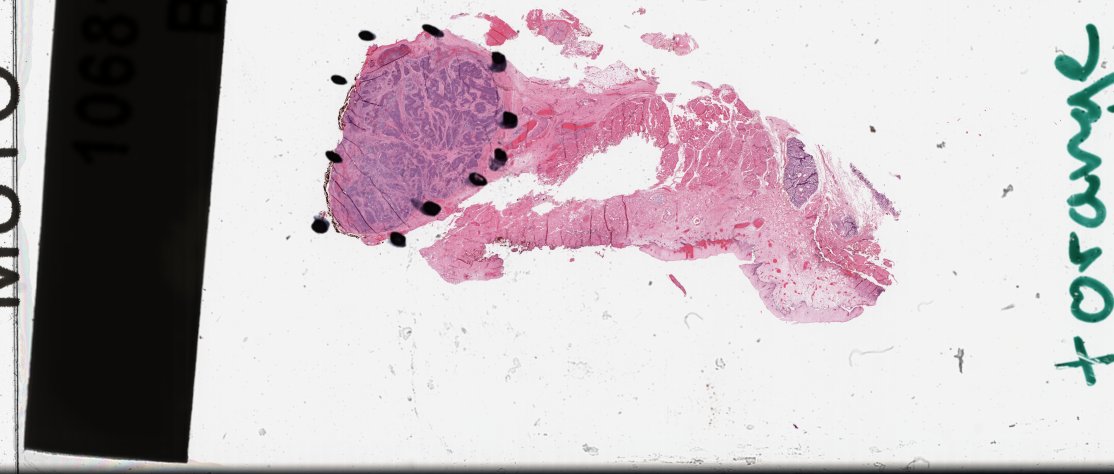

Example Slides

Below are some example slides highlighting the robustness of our model in the presence of artifacts.

To try our model on your own slides, visit our demo.

TCGA-BH-A0DK-01Z-00-DX1 slide with necrosis

TCGA-BH-A0DK-01Z-00-DX1

Necrosis is not caught by most methods.